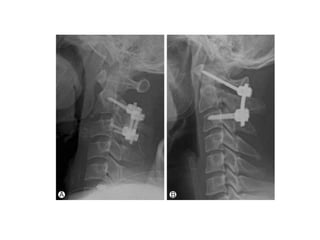

Surgical stabilization

• C1 – type II odontoid combination # with d >

5mm.

• C1 – hangman combination # C2-3 angulation

> 11 degree

• 66.

Surgical stabilization • C1– type II odontoid combination # with d > 5mm. • C1 – hangman combination # C2-3 angulation > 11 degree